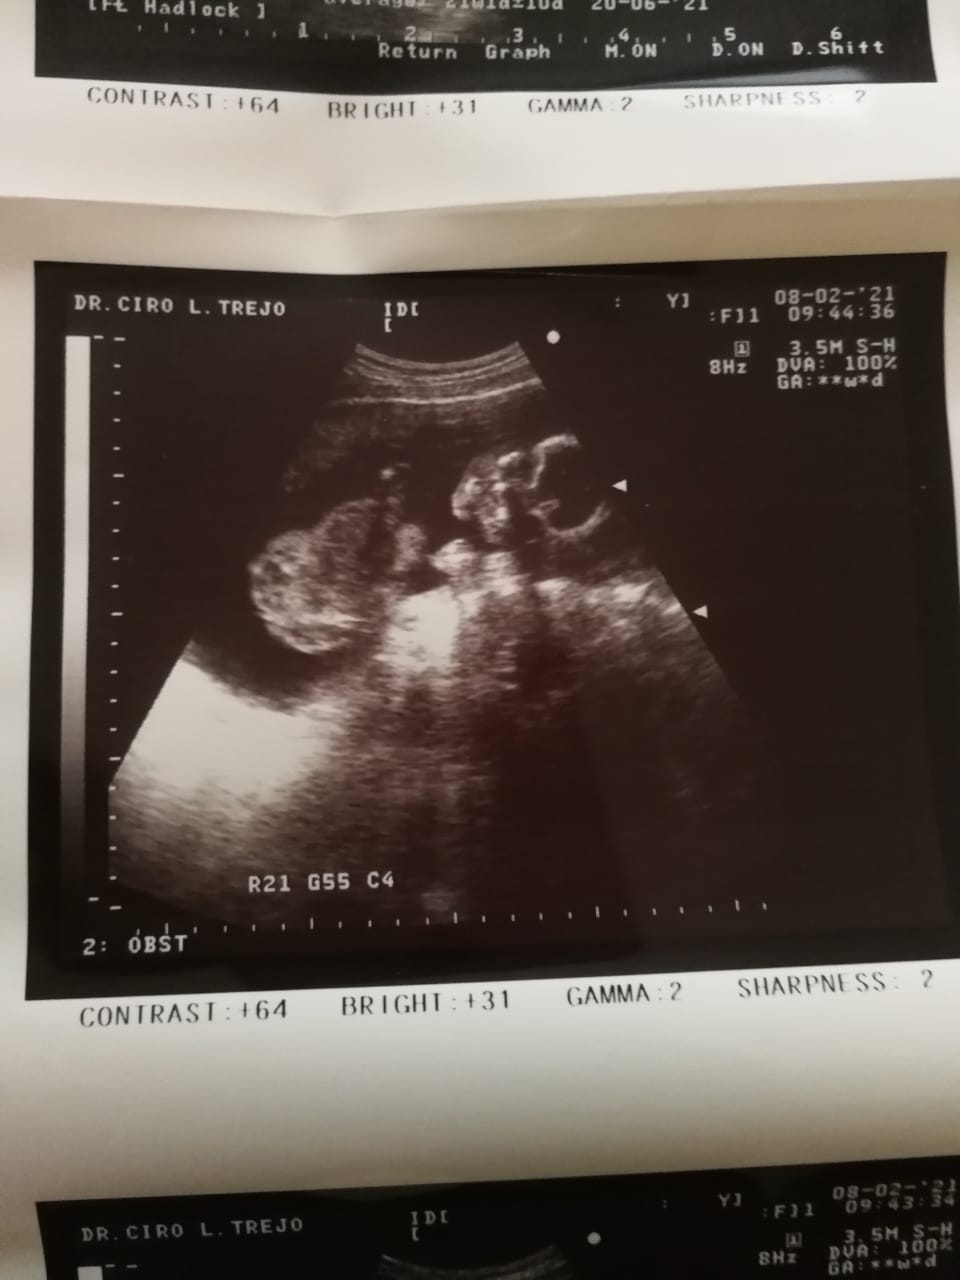

I’ve been pregnant four times. Each time we found out, we were overjoyed—filled with hope and excitement. But that happiness was always cut short. Every single pregnancy ended in miscarriage. The pain is indescribable. Each loss sent me into a deep depression, grieving the baby we had already begun to love. Through it all, my husband has been my rock, holding me up and reminding me not to give up on our dream.